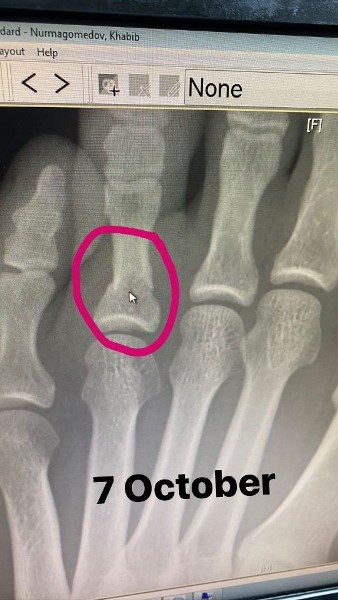

Первое фото, сделанное 7 октября, представляет собой рентгеновский снимок левой стопы. Второе фото, сделанное 8 октября, — обычный снимок того же участка.